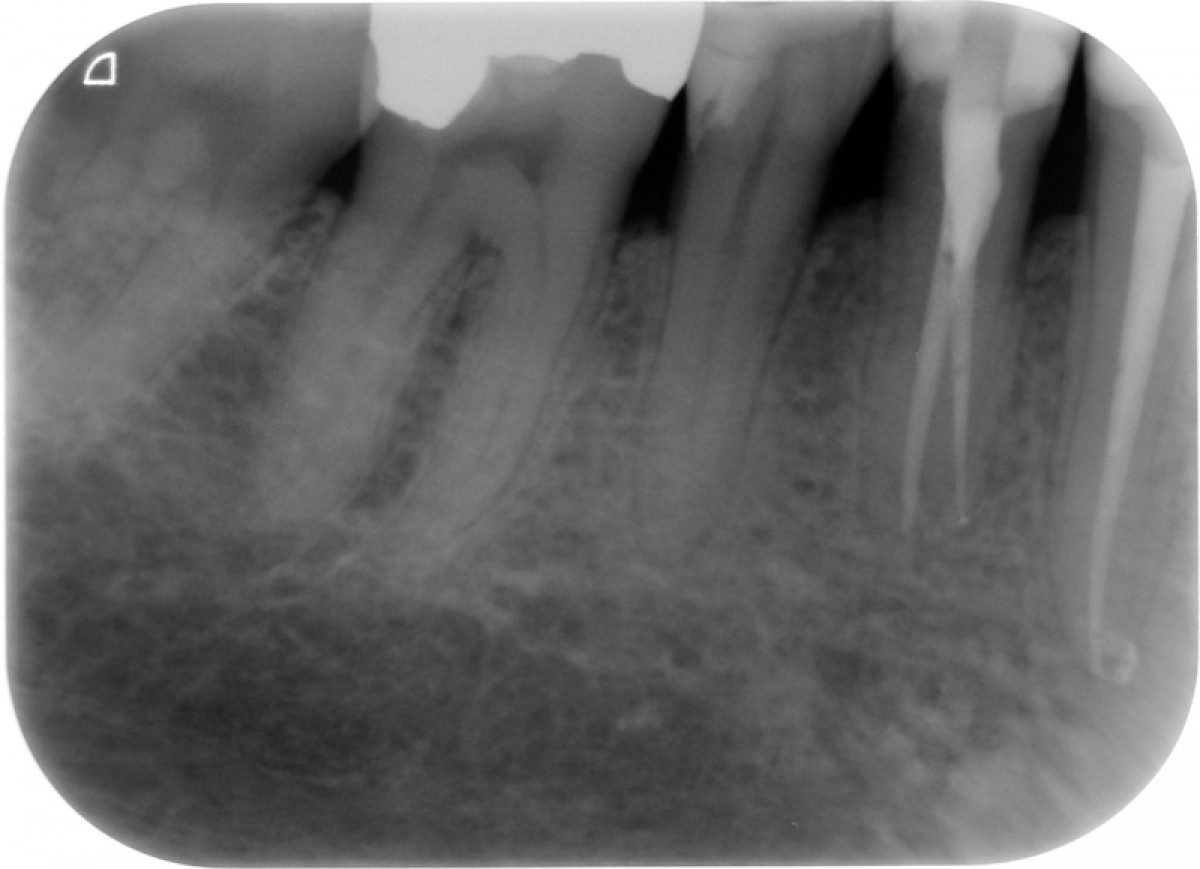

The gutta-percha point inserted into the root canal properly, adapting it to a size almost equal to the one employed to shape the apical terminus. Not wider, not smaller. Here are exposed a couple of cases made by shaping the root canal with a NiTi instrumentation technique and followed up for 9 to 12 months (Fig. 1-6).

It’s encouraging its easy handling and quite precise adaptation to the apical part of the root canal. The periapical healing, assessed by 2D-Rx, is considered satisfactory but further analysis and clinical studies related to these particular cements should be performed to confirm the first encouraging results.